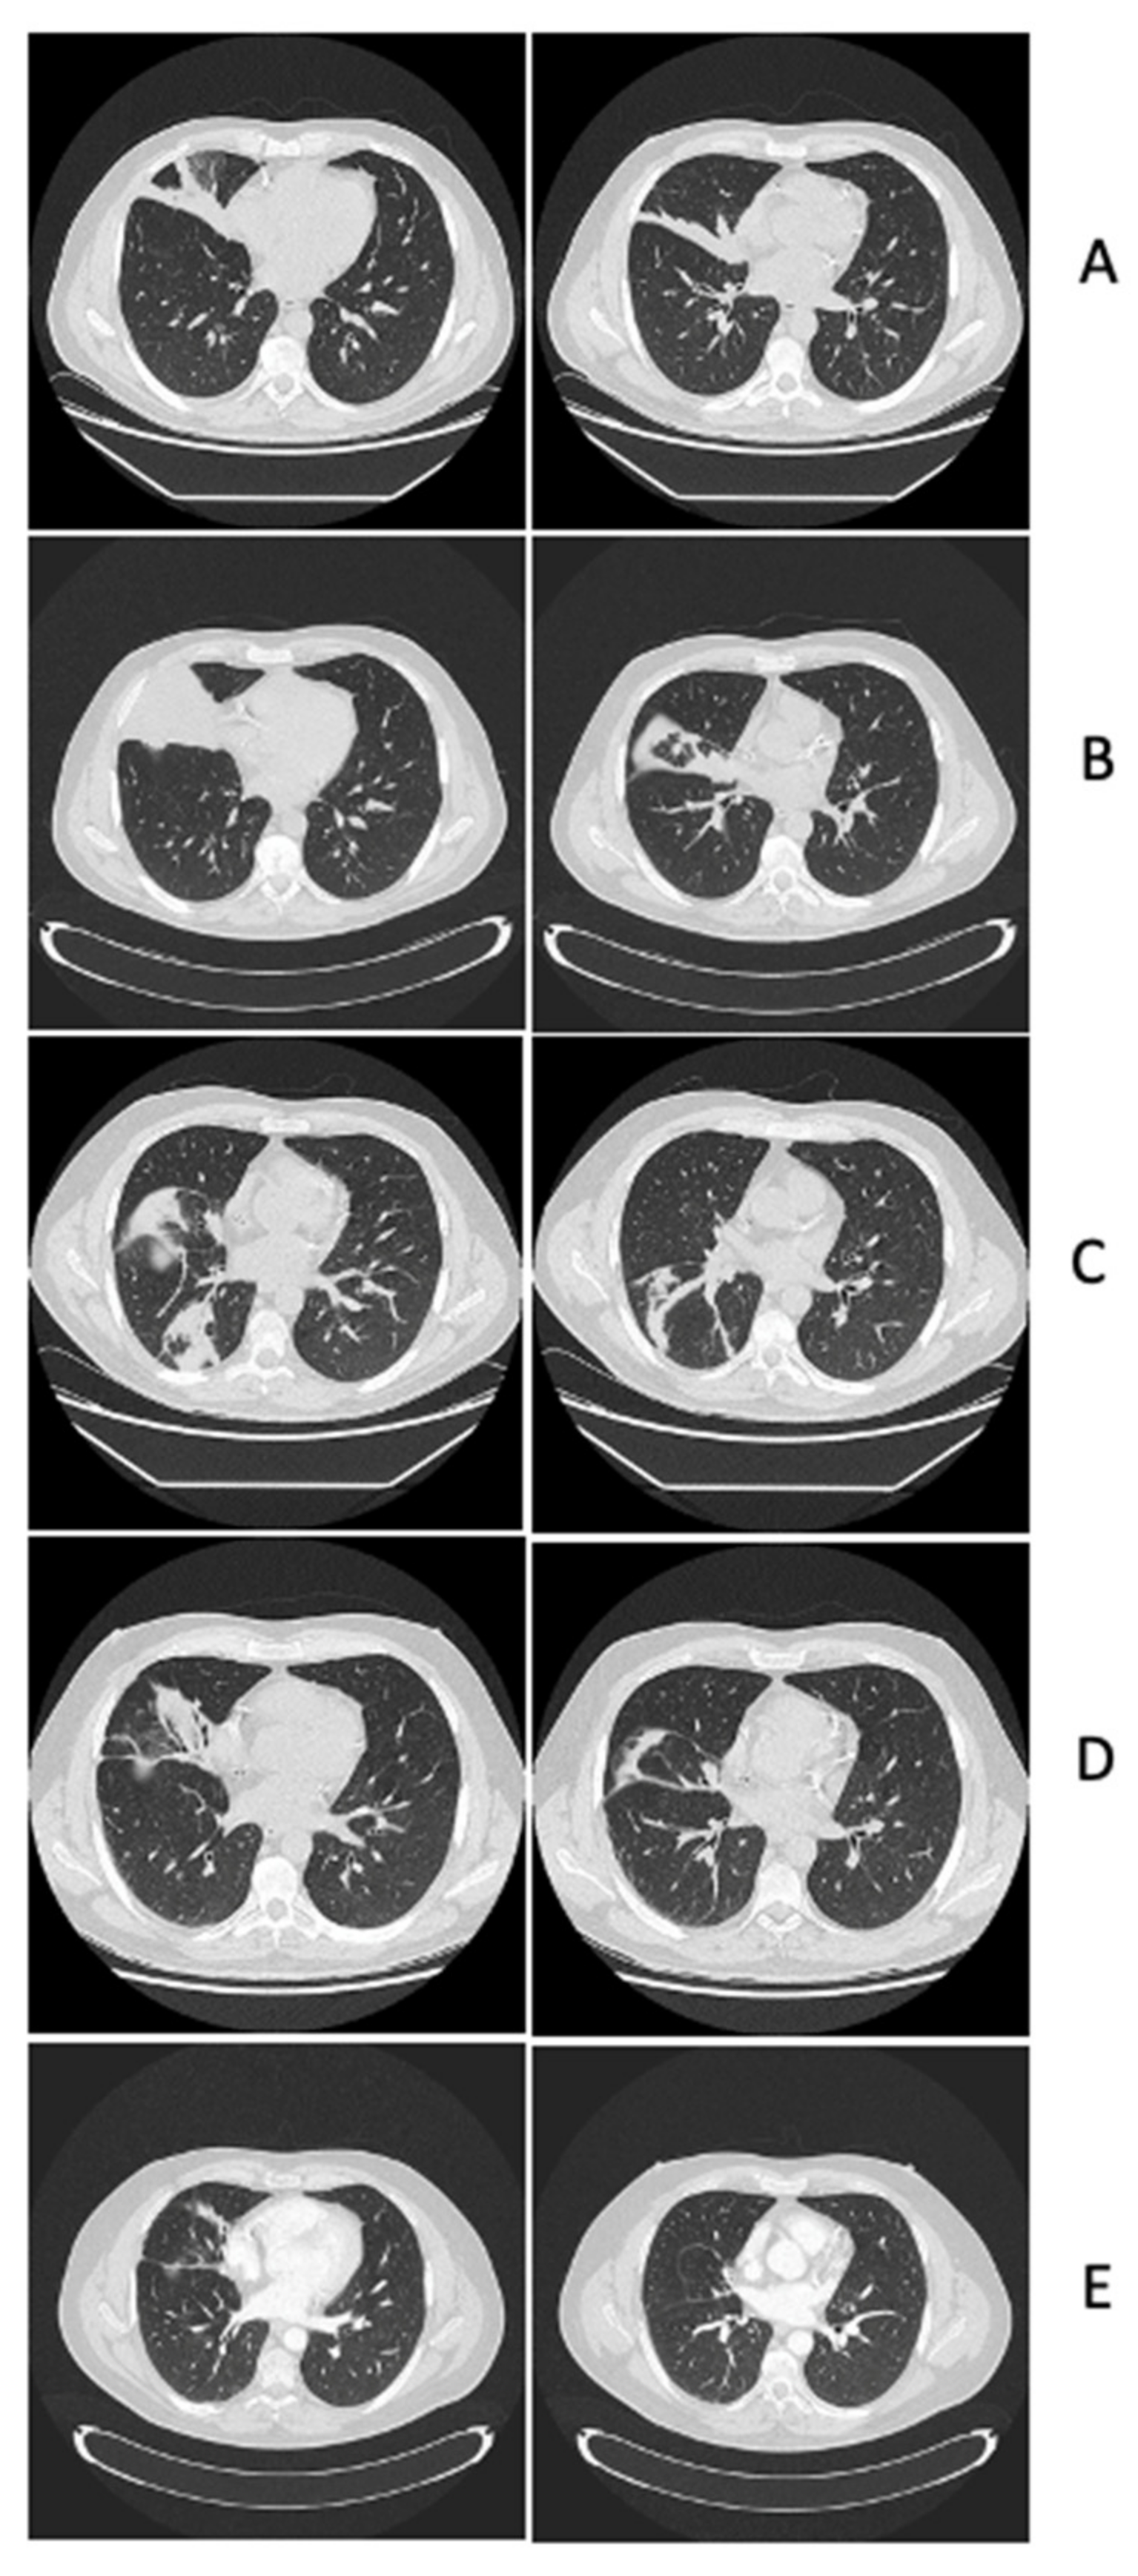

2.1. Leukaemia Diagnosis, Infectious Complications of Remission Induction and Consolidation Chemo-Therapies, Diagnosis and Management of Central Nervous System Lesions

2.2. Clinical and Neuroimaging Follow-Up of Central Nervous System Infectious Lesions

2.2.1. Case Presentation